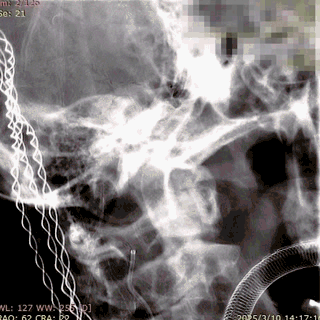

第二枚3*25支架沿017支架微导管上高。

第二枚支架远端释放。

第二枚支架释放至中段。

中段释放适当推挤系统,保持贴壁良好。

中段释放后造影。

继续释放支架。

继续释放支架,造影观察贴壁良好。

完全释放支架。

支架微导管沿推送导丝上高并将推送导丝撤出。

术后即刻造影。

术后重建。